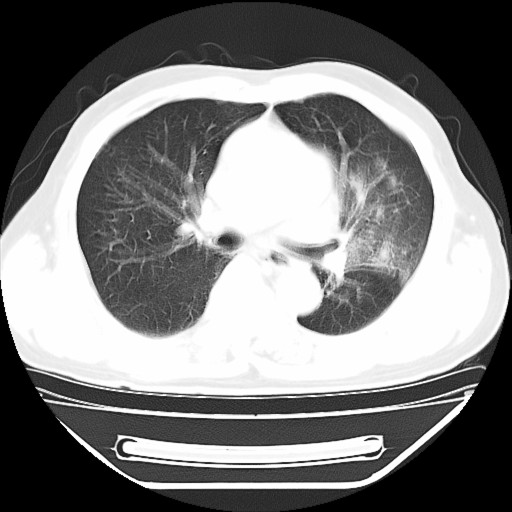

以下是引用hhcckk在2009-5-29 10:34:00的发言:[br]左下肺片絮状边缘模糊影,考虑感染,建议治疗后复查[br]